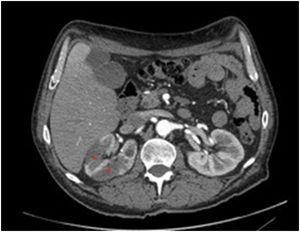

Varón de 54 años de edad con antecedentes personales de hipertensión arterial, diabetes mellitus tipo 2, hipercolesterolemia, infarto de miocardio que requirió colocación de stent en descendente anterior y fumador activo. Estaba en tratamiento con ácido acetilsalicílico, simvastatina, enalapril, atenolol, metformina, insulina, furosemida y omeprazol. Consulta por segunda vez en 24 horas en el Servicio de Urgencias por dolor abdominal y vómitos de dos días de evolución. A la exploración física presentaba una presión arterial de 139/85 mmHg y una frecuencia cardíaca de 45 latidos por minuto, con una auscultación cardíaca y abdominal sin soplos. En la analítica destacaba una lactato deshidrogenasa de 2458 UI/l, siendo la previa del día anterior inferior a 500 UI/l, con creatinina de 0,84 mg/dl y urea de 28 mg/dl. El electrocardiograma mostraba T aplanadas en derivaciones precordiales. Se solicitó una tomografía computarizada con contraste endovenoso abdominal (figura 1 y figura 2), en la que se observó ateromatosis aórtica infrarrenal y de ambas ilíacas comunes con múltiples áreas hipodensas en el riñón derecho de morfología triangular con base cortical, que sugerían infartos renales. Se ingresó para completar el estudio y control de los factores de riesgo cardiovascular. En las pruebas complementarias destacó una hemoglobina glicada de 8,7 % y microalbuminuria con un índice albúmina/creatinina de 42 mg/g. La ecografía Doppler renal fue normal, pero la ecocardiografía transtorácica mostró hipoquinesia anteroseptal con fracción de eyección en el límite inferior de la normalidad. Se descartó retinopatía diabética en el fondo de ojo. Se inició terapia anticoagulante con antagonistas de la vitamina K, y se intensificó la insulinización y el control de la hipertensión arterial, sustituyéndose el enalapril por lisinopril. Actualmente es seguido conjuntamente en consultas de Nefrología y Medicina Interna, con buen control de los factores de riesgo cardiovascular y sin deterioro de la función renal.

Figura 1. Áreas de infarto renal (asteriscos rojos) visualizadas como imágenes hipodensas en la tomografía computarizada abdominal